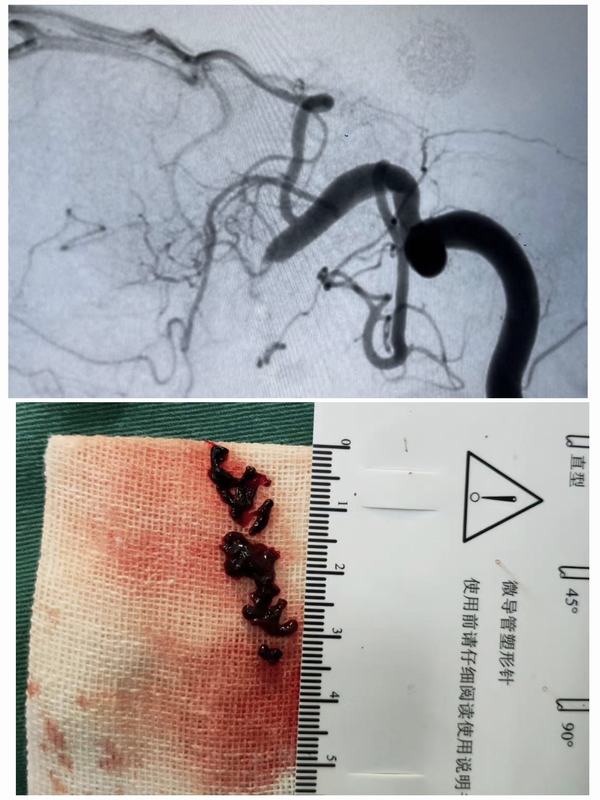

2月23日中午12:00,脑病急诊科接诊一名59岁女性患者,急性起病,主因:突发左侧肢体无力1.6小时。经查体患者神志清,精神差,言语不利,左侧肢体肌力0级。立即开通绿色通道,急查头颅CT示:右侧基底节区及右侧侧脑室前角旁多发腔梗。家属签字同意后给予静脉溶栓治疗。12:20患者进入导管室行全脑血管造影+动脉溶栓术+机械取栓术。患者于3月3日出院,出院时患者神志清,精神状态良好,左侧肢体肌力正常、言语清晰,入院时症状得到完全缓解。

脑卒中具有高发病率、高致残率、高死亡率、高复发率的特点,给社会、家庭带来了沉重的负担,但只要4.5-6小时内进行静脉溶栓,必要时动脉取栓的积极治疗,多可获得更好的疗效。